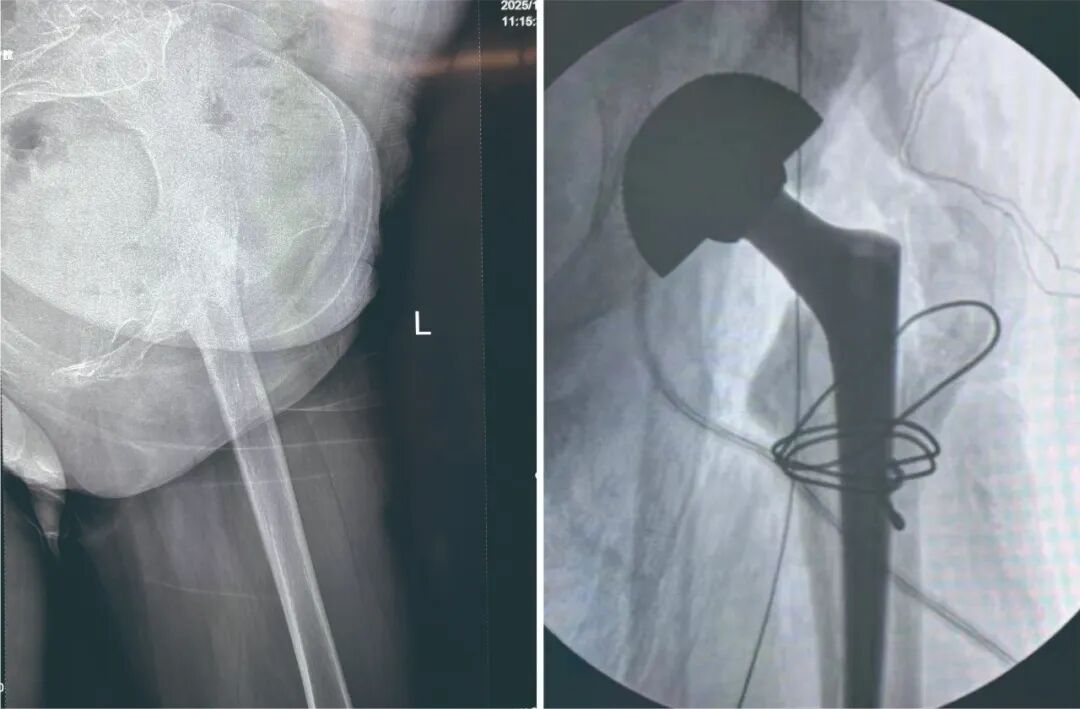

术前左侧关节(左)术后左侧关节(右)

置换的假体

术中根据刘阿姨病情特点和骨骼结构,选取了适配的髋关节假体,凭借精湛技艺小心翼翼地植入,每一个步骤都严格把控角度、深度,确保假体与骨骼完美贴合,为日后的功能恢复奠定基础。经过数小时的奋战,手术宣告成功。